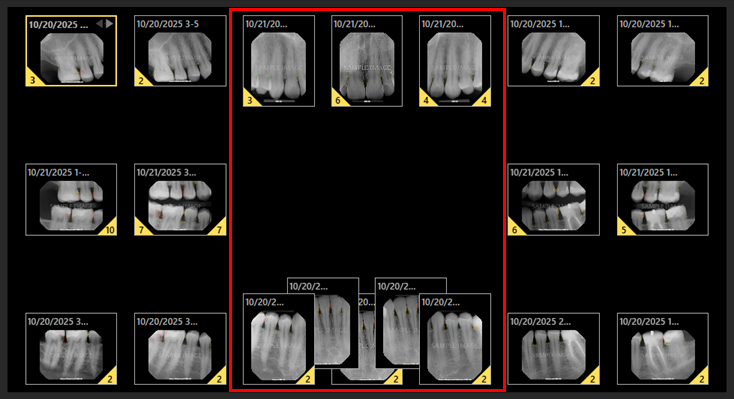

Five Anterior Image Positioning Option

In the Modality View, a Use Five Anterior Positioning checkbox has been added to the options for both the Intraoral X-ray and Intraoral Color modalities.

With this checkbox clear, three anterior image positioning is used.

With this checkbox selected, five anterior image positioning is used.